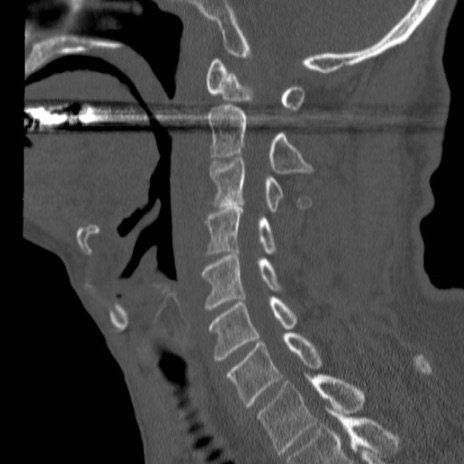

症例46 頚椎CT(矢状断像)

【症例】80歳代男性

【主訴】両側頚部〜上肢のしびれ

【現病歴】昨日、自宅内で転倒、その後より上記症状あり。意識障害なし。

【身体所見】両側上肢のallodynia(熱痛覚過敏)あり。MMTおよびDTRは正確な所見取れず。両上肢の挙上はなんとか可能。

異常所見と診断は?